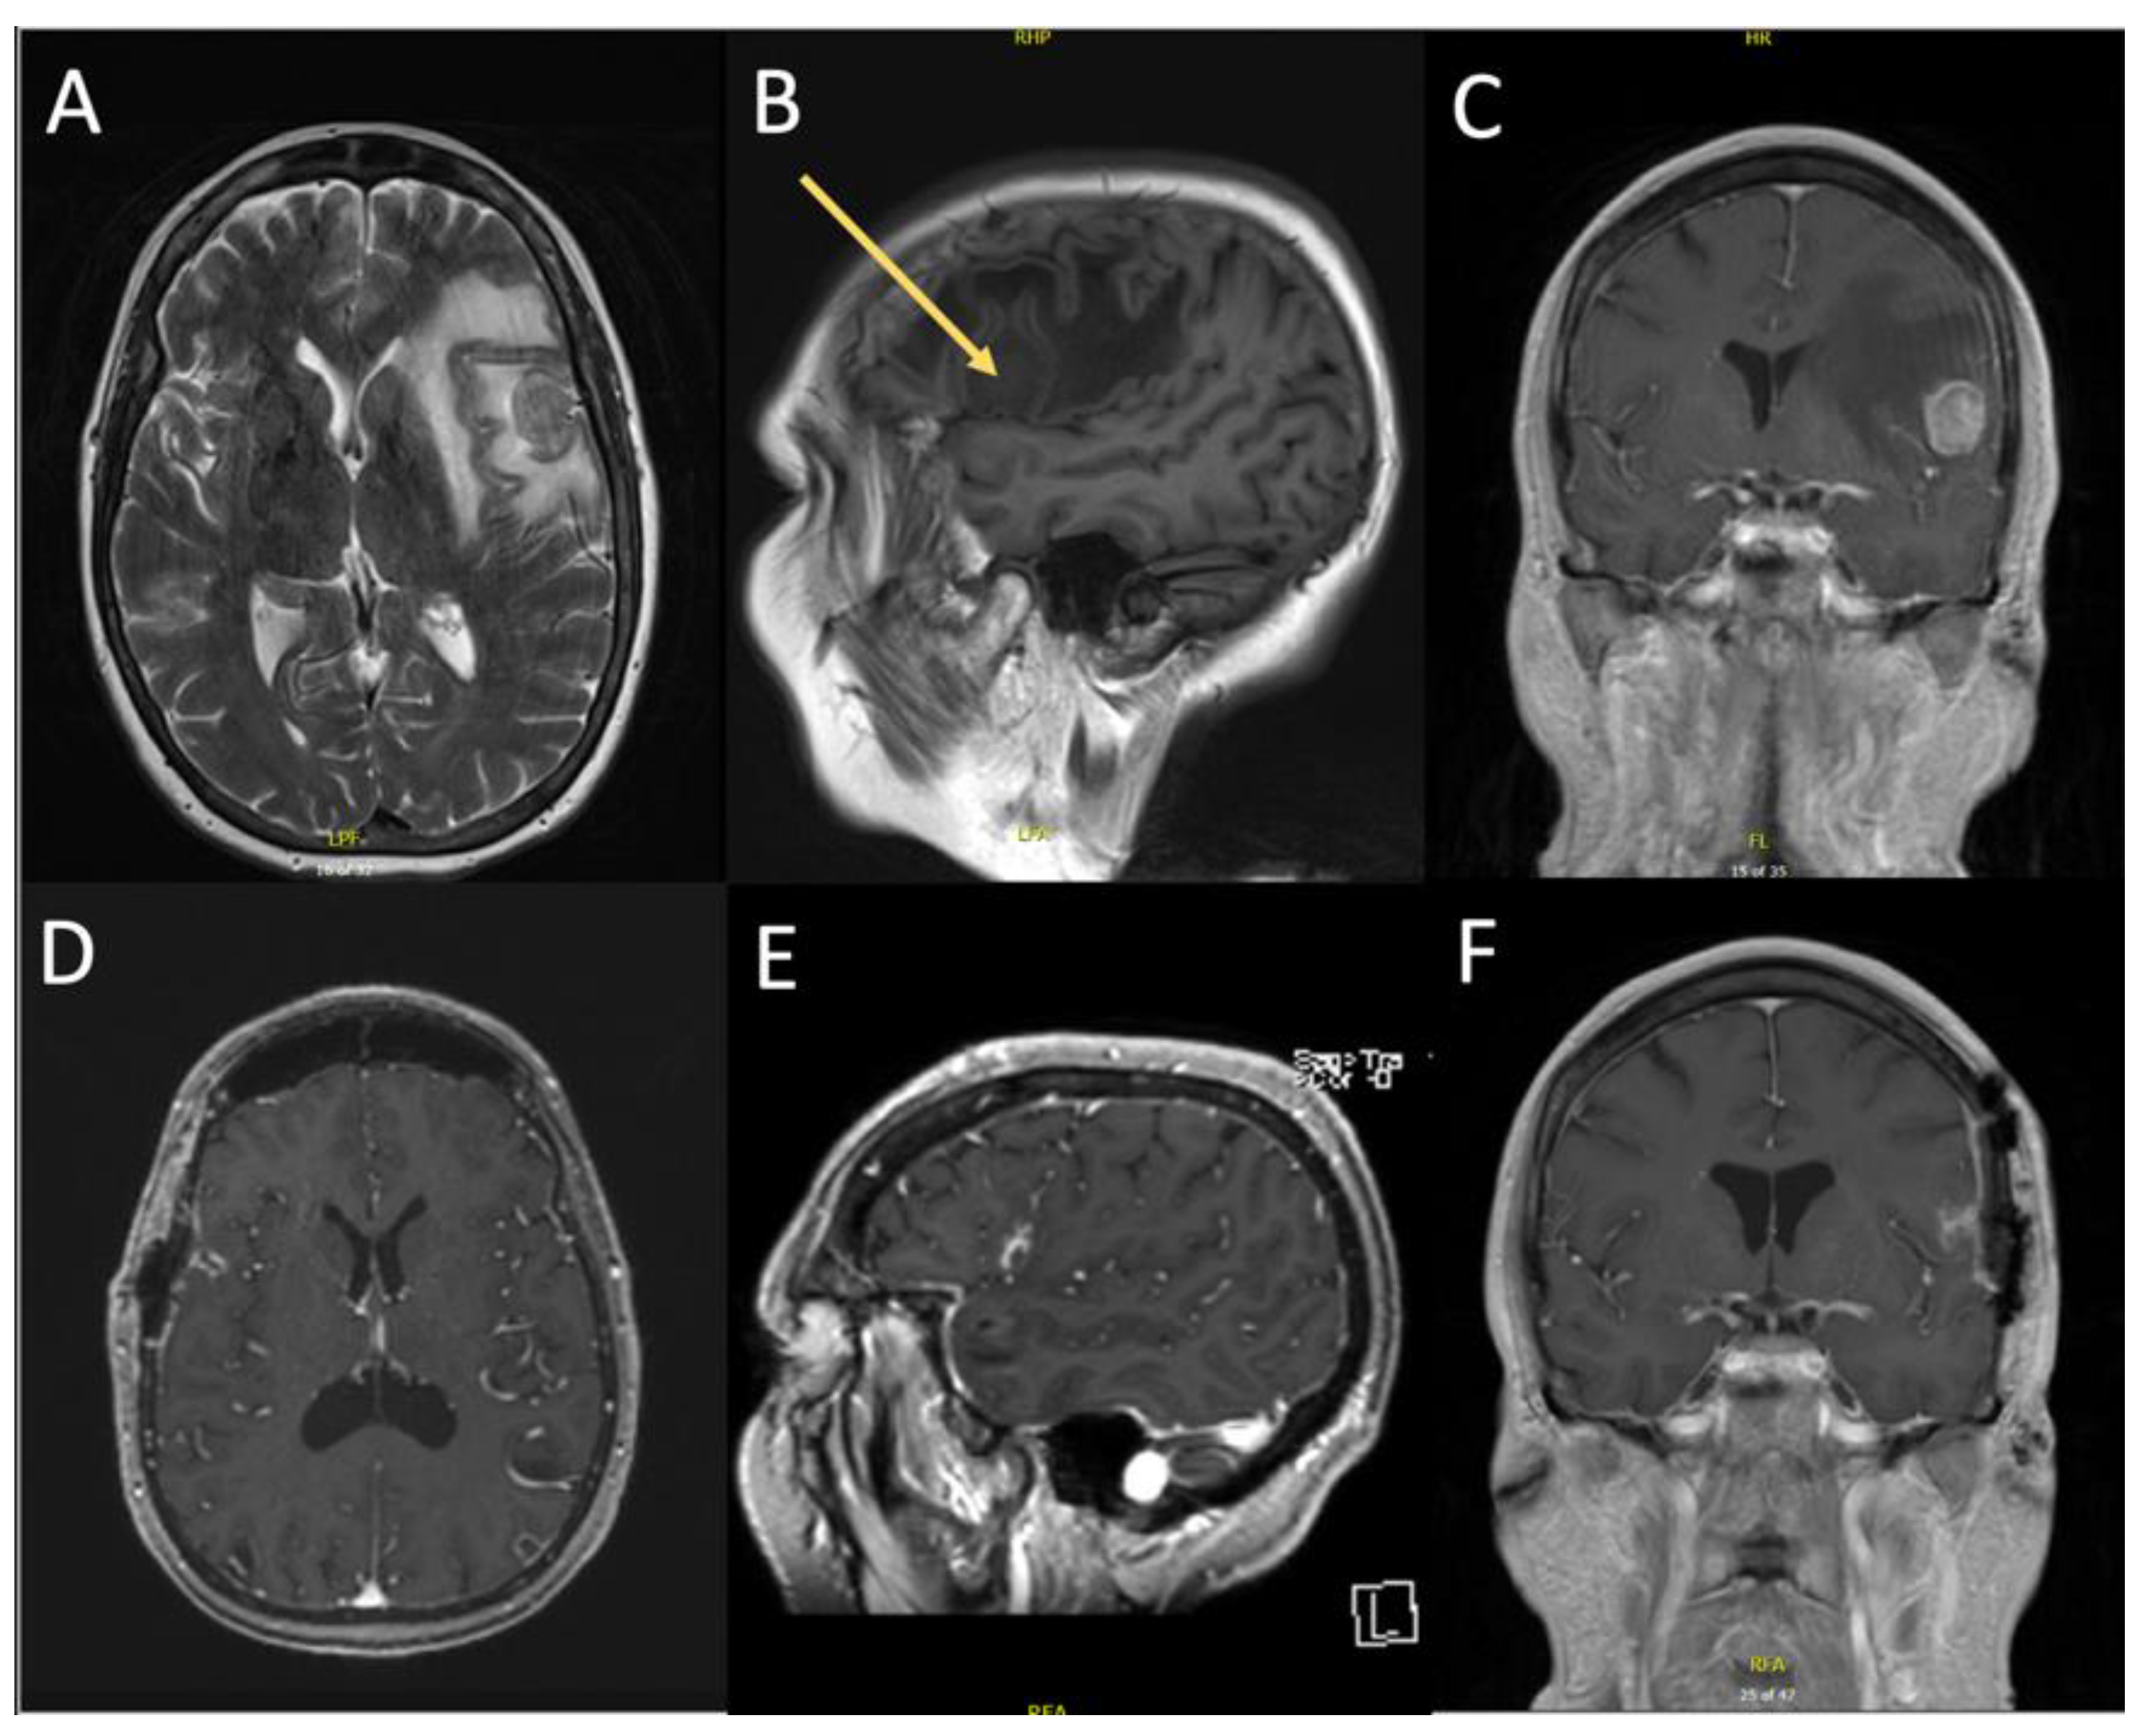

3.2.1. Case 1

3.2.2. Case 2